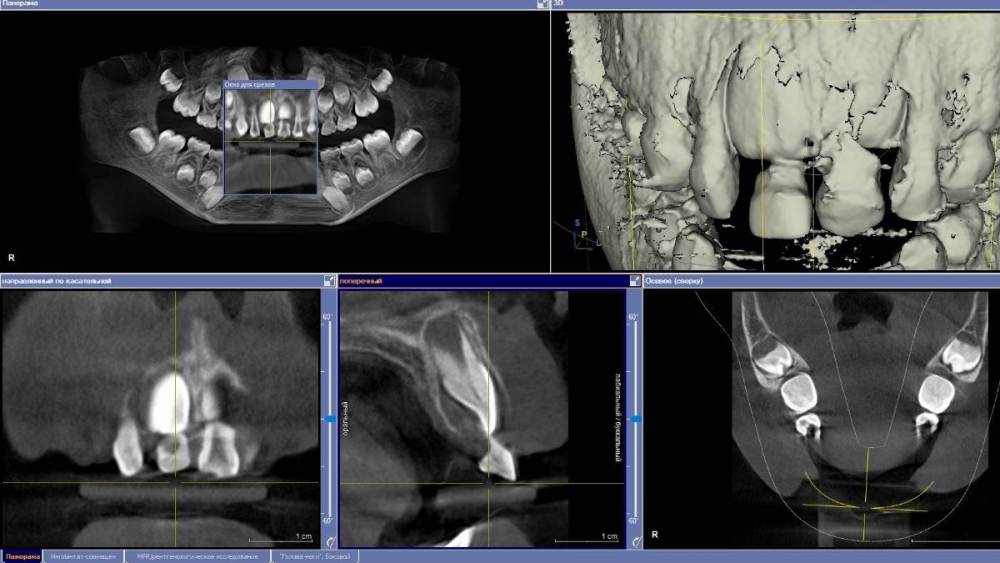

Ponchik Опубликовано 9 декабря, 2021 Поделиться Опубликовано 9 декабря, 2021 Пациентка 6.5 лет. Сегодня пациентка получила травму. Кожа губ без ссадин. Слизистая верхней губы с очень маленькими ссадинами. Центральные молочные резцы подвижны, при движении одного двигается и второй (по КЛКТ участок альвеолярного отростка между 51 и 61 сломан) круговая связка 51 вестибулярно сохранена (в акте дыхания почти участвует), у 61 сохранена полностью. Отмыл, пальцами на 1.5-2 мм выдвинул 5.1, переместил в правильное положение и приклеил на композит ленту на 4 резца (орто лигатур в клинике нет) Сижу теперь и думаю а нужно ли? Корни почти резорбировались. Смена не за горами. PS. Анамнез отягощен - пациентка моя дочь, действовал не автопилоте, детский приём не веду ни в какой форме. Может удалить резцы? Или оставить, но вдруг воспаление? Переход воспаления на зачатки постоянных и т.д. Что делать? Ссылка на комментарий